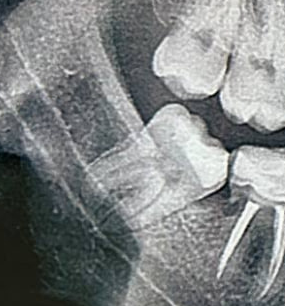

мезиальный прикус, пара зубов на верхней челюсти стоит 2 рядом при этом зубы мудрости сверху выросли нормально

какие шансы просто поставить брекеты и обойтись без операций?

Мне вот зубы мудрости, правда ретинированные, удаляли как раз перед брекетами. Зубы мудрости крупные и сдвигают зубы другие, скучивая их.

Чаще всего рекомендуют их удалить. Потому что после исправления прикуса не факт что зм не поднасрут опять.